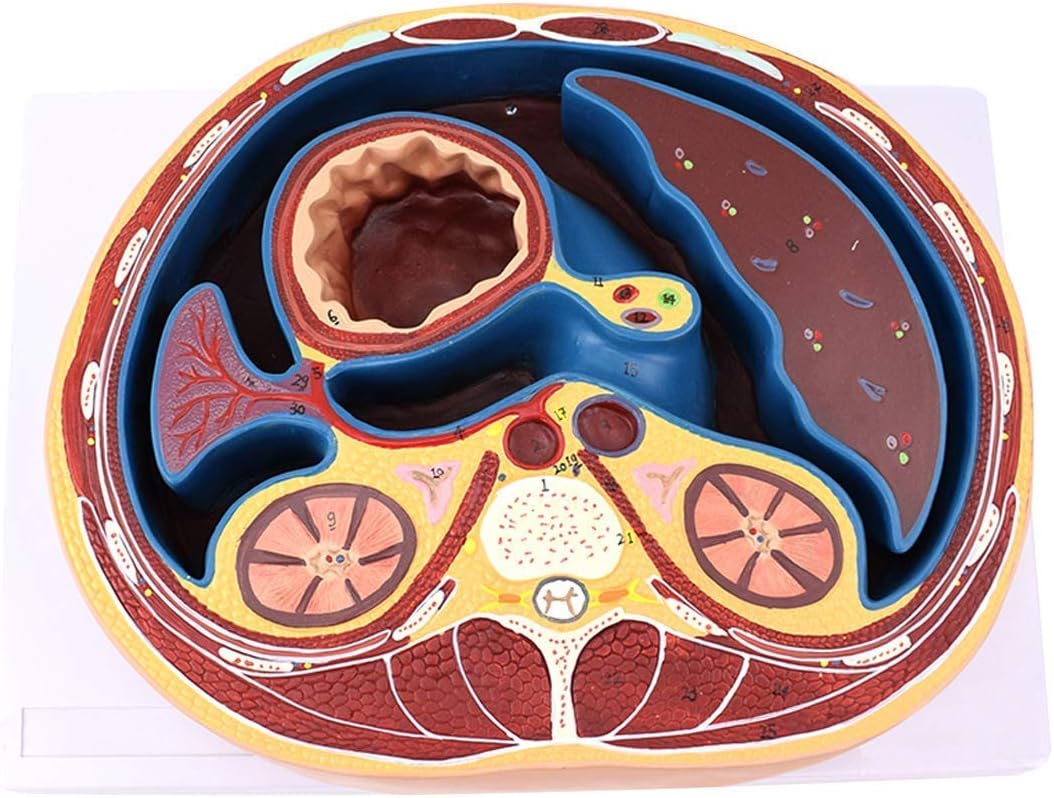

faculty.etsu.eduHuman Abdomen Model Medical Anatomical Flat Membrane Capsule Structure

faculty.etsu.eduHuman Abdomen Model Medical Anatomical Flat Membrane Capsule Structure

Abdominal Muscle Layers, Artwork - Stock Image - C010/7080 - Science

www.sciencephoto.comabdominal muscle layers

www.sciencephoto.comabdominal muscle layers